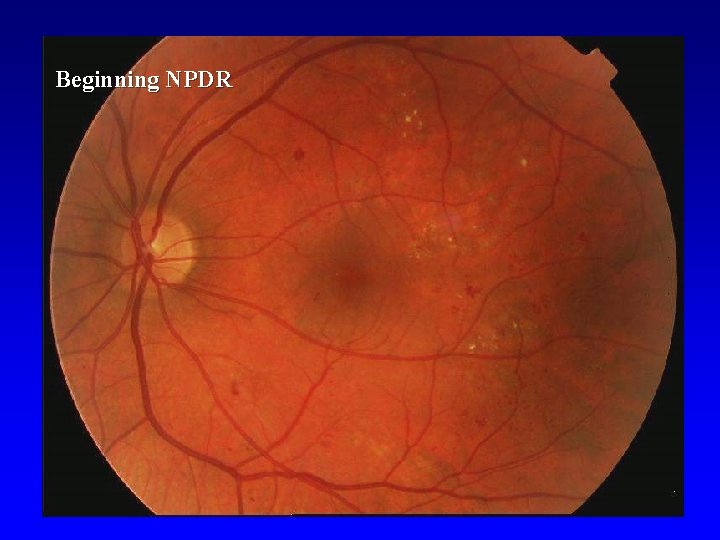

Nonproliferative DR (NPDR) • • • Beginning Intermediate Advanced

Beginning NPDR